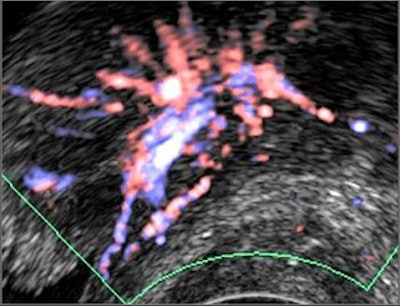

Freehand scanning was used for 3D data acquisition, and surface rendering and multiplanar reconstruction for 3D data analysis. Power Doppler ultrasound was used to differentiate the extent of infiltration. The criteria for staging were based on the vascularity of the tumor's basement. The gold standard was the histomorphology results.

| Power Doppler ultrasound criteria for staging vascularity of the tumor basement. Above, submucosal vessels; second, half muscle wall vascular. Below, whole muscle wall vascular; second image, few vessels in the perivesical walls; third image, massive flow in the perivesical fat. Images courtesy of Dr. Veronika Gazhonova, Russian President Medical Center and Russian State Medical University. |